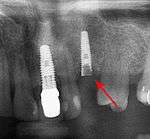

Fracture of an implant and abutment screw is a catastrophic failure and the fixture cannot be salvaged.

Fracture of abutment screws (arrow) in 3 implants required removal of the remainder of the screw and replacement.